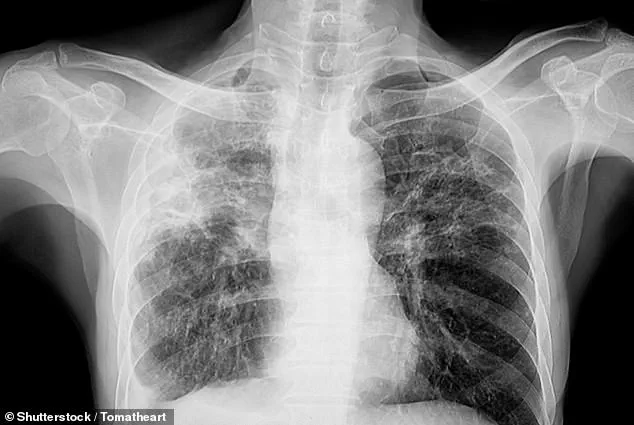

With over 70,000 Britons currently living with pulmonary fibrosis, a condition that scars lung tissue and reduces oxygen intake, the risk of vision loss is becoming an urgent public health concern.

More than 70,000 Britons are currently living with pulmonary fibrosis, a chronic disease which causes lung tissue to become damaged and scarred, making breathing difficult and reducing the amount of oxygen entering the blood.

Pulmonary fibrosis is not just a respiratory issue—it is a systemic problem that can compromise multiple organs, including the eyes.

The reduced oxygen levels in the blood, a hallmark of the disease, can lead to a cascade of complications, with the eyes being particularly vulnerable.